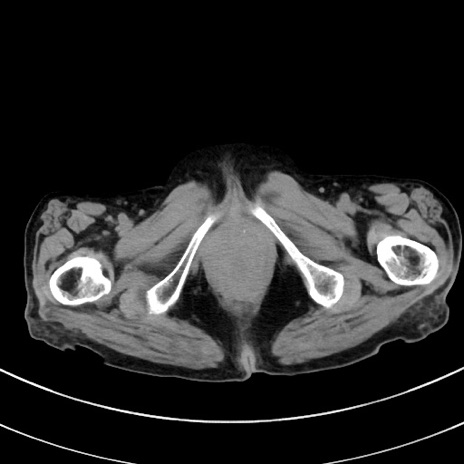

症例33(横断像)

【症例】70歳代 女性

【主訴】心窩部痛

【現病歴】延髄病変の精査・加療にて神経内科入院中。本日より心窩部痛あり。

【身体所見】右下腹部を中心に圧痛と反跳痛あり。